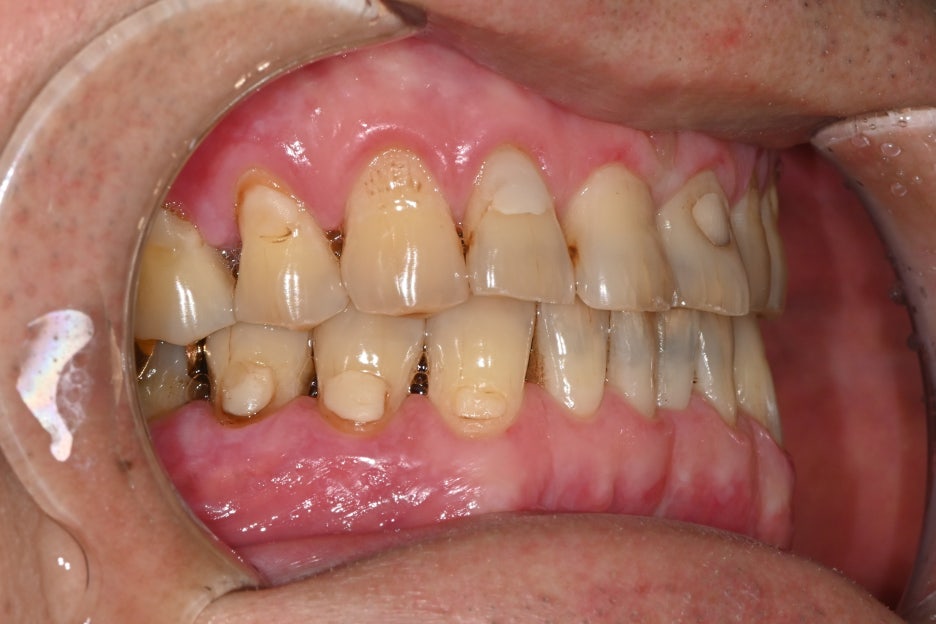

The patient visited with the chief complaint that “the lower left molar was extracted a long time ago, and lately I’ve been chewing only on the other side, so my jaw feels uncomfortable.”

Because the tooth had been missing for a long time, the bite was unbalanced on both sides, and the patient said food often got stuck and the gums felt uncomfortable.